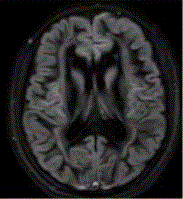

问题 女性,21岁,部分性癫痫,MR表现如下图,可能的诊断是

选项 A.神经纤维瘤病I型 B.神经纤维瘤病II型 C.结节性硬化 D.带状型灰质异位 E.颜面血管瘤综合征

答案 D